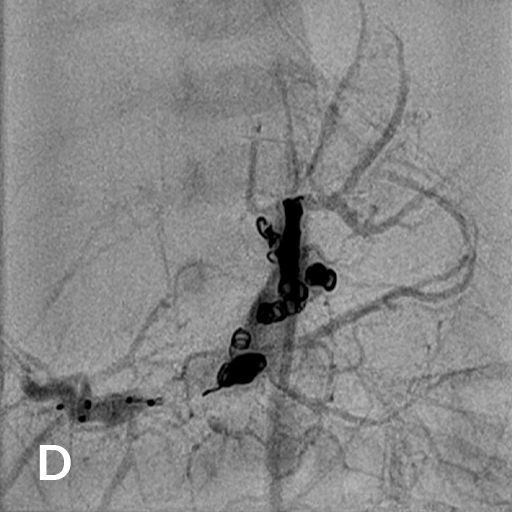

Ausgedehntes fokales Leberhämangiom eines Neugeborenen

Reifes Neugeborenes mit Hepatomegalie und Herzinsuffizienz. Das MRT der Leber (A) zeigte ein ausgedehntes kongenitales Hämangiom mit normalem Lebergewebe in den Randbereichen vor allem links. Deutlich gestaute Lebervenen (B) infolge der Rechtsherzbelastung. Die Kontrastmittelinjektion die Arteria hepatica dextra (C) zeigt mehrere arterielle Feeder mit rascher Parenchympassage. Nach interventionellem Verschluss mittels 3 Vascular Plugs und insgesamt 28 Volumen-Coils deutliche Reduktion des Shunt-Flusses im rechten Leberlappen mit noch verbleibenden Hämangiomanteilen links (D).